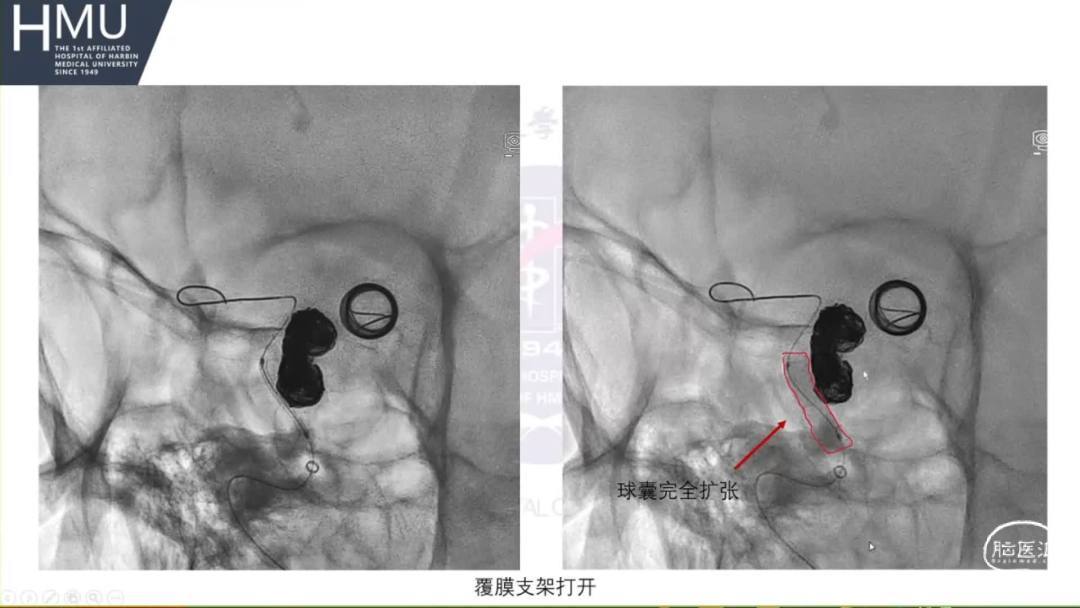

21:00覆膜支架置入术